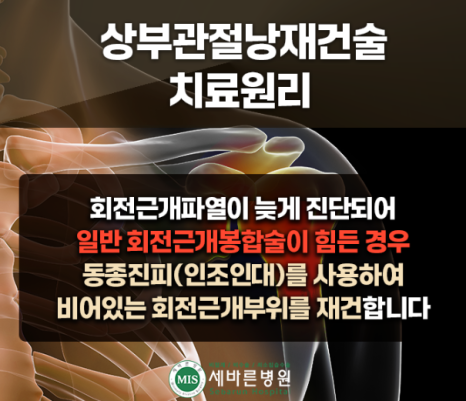

이제는 의료기술의 발달, 첨단 의료기기의 보급으로 인해 회전근개 재파열 또는 어깨힘줄이 완전히 다 끊어져서 팔을 못 들어 올리는 환자분들도 ⭐마지막 단계인 인공관절 수술을 하지 않고도 내시경을 이용하여 자기의 관절을 그대로 사용할 수 있는 치료방법이 고안되었습니다. 바로✅상부관절낭재건술이라고 하는 방법인데요. 지금부터 알아보겠습니다.

회전근개파열을 늦게 진단받았거나 일반 회전근개 봉합술 적응증이 안 되는 경우, 어깨 재수술을 해야 하는 경우에 시도할 수 있는

어깨 치료방법으로 세바른병원의 상부관절낭재건술 치료방법이 있는데요, 비어있는 회전근개 범위가 커서 봉합술이 불가능하다 판단될 경우에도 서초동 정형외과 세바른병원의 상부관절낭재건술을 통해 동종진피,인조인대를 사용하여 비어있는 회전근개 부위를 재건할 수 있습니다.

상부관절낭재건술(SCR)치료는 손상받은 어깨 회전근개 힘줄 부위에 기증받은 “동종진피(인조인대)를 이식하여, 손상된 관절을 다시 살려내고 본인의 관절을 그대로 유지하며 어깨를 정상적으로 사용할 수 있게 해주는 최소침습 관절내시경 치료”입니다.

상부관절낭재건술은 일본의 Mihata 등이 고안한 수술법으로 최초에는 환자 본인의 대퇴근막을 허벅지에서 떼어내어 손상되어 없어져 버린 회전근개를 대신하여 어깨관절에 이식하는 치료법으로 시작하였으나, 이런 방법은 이식근막을 떼어낸 부위인 허벅지에 상처 및 통증이 추가로 발생하며, 이식건을 채취하고 다듬는데 걸리는 수술시간이 추가되고, 채취건의 질과 양을 예측하기 어려워, 최근에는 이런 자가대퇴근막을 대신하여 ⭐이식 거부반응을 제거한 동종진피(ADM; Acellular Dermal Matrix; 인공인대)를 기증받아 사용하여 내시경 상부관절낭재건술을 진행하고 있습니다.